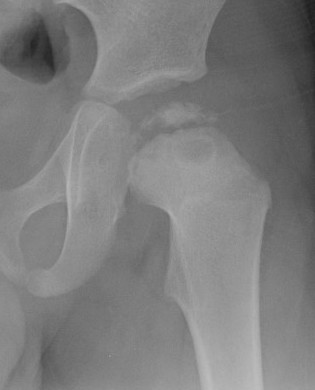

Septic arthritis

SCFE / Perthes

southwickPerthes